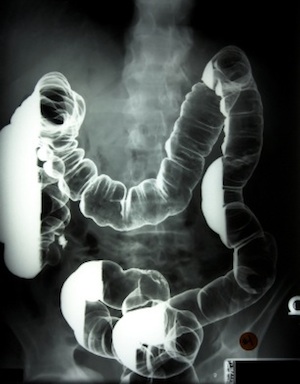

Barium salts can improve x-ray imaging and certain radiological procedures require that patients drink a barium sulfate beverage; perhaps you or someone you know have been lucky enough to receive a barium enema prior to a colon x-ray? In 2003, it was reported that a contaminated barium solution had been linked to 44 suspected cases of barium toxicity and as many as 9 deaths. Following this tragedy, the CDC recommends patients and clinicians be mindful of barium toxicity after radiologic procedures. [3]